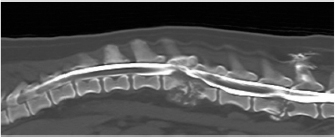

Hematology and comprehensive biochemistry and radiographs of the thorax and abdomen were performed. Abnormalities on hematology and serum biochemistry included a slight neutrophilia and monocytosis, and a mild elevation in urea and total protein. The patient was sedated with methadone (0.3 mg/kg IV) and acepromazine (0.02 mg/kg IV), induced with propofol (1 mg/kg IV) and general anesthesia maintained with isofluorane. Plain radiographs of the entire vertebral column and thorax, and a computed tomography (CT) scan (Toshiba Aquilion; Zoetermeer, The Netherlands) of the lumbar spine following intra-thecal injection of iomeprol 0.3ml/kg (Iomeron 250 mg/ml; Bracco.p.a, Milan, Italy) at L5–L6 subarachnoid space were performed. Findings included lysis of the caudal endplate of L2 and cranial endplate of L3, and a pathologic fracture of the caudal metaphysis of L2 causing subluxation (Fig. 1). These bony changes were associated with isoattenuating material causing ventral extradural spinal cord compression at that level. The above description was consistent with discospondylitis, osteomyelitis and a pathological fracture with subsequent vertebral subluxation, and epidural empyema. Similar but less severe lesions were found in L5–L6 with minimal spinal cord compression.

Fig. 1. Computed tomography reconstructed sagittal image of the thoracic and lumbar spine illustrating lysis on the caudal endplate of L2 and cranial endplate of L3, with irregular and poorly defined margins; an irregular periosteal reaction of the lateral aspects of the vertebral bodies and vertebral arch, and a pathologic fracture of the caudal metaphysis of L2 causing subluxation. These bony changes are associated with isoattenuating material along the ventral and ventrolateral aspect of the vertebral canal over the vertebral bodies of L2 and L3, causing ventral extradural spinal cord compression. Similar but less severe lesions were found affecting L5–L6 with minimal ventral compression of the spinal cord.